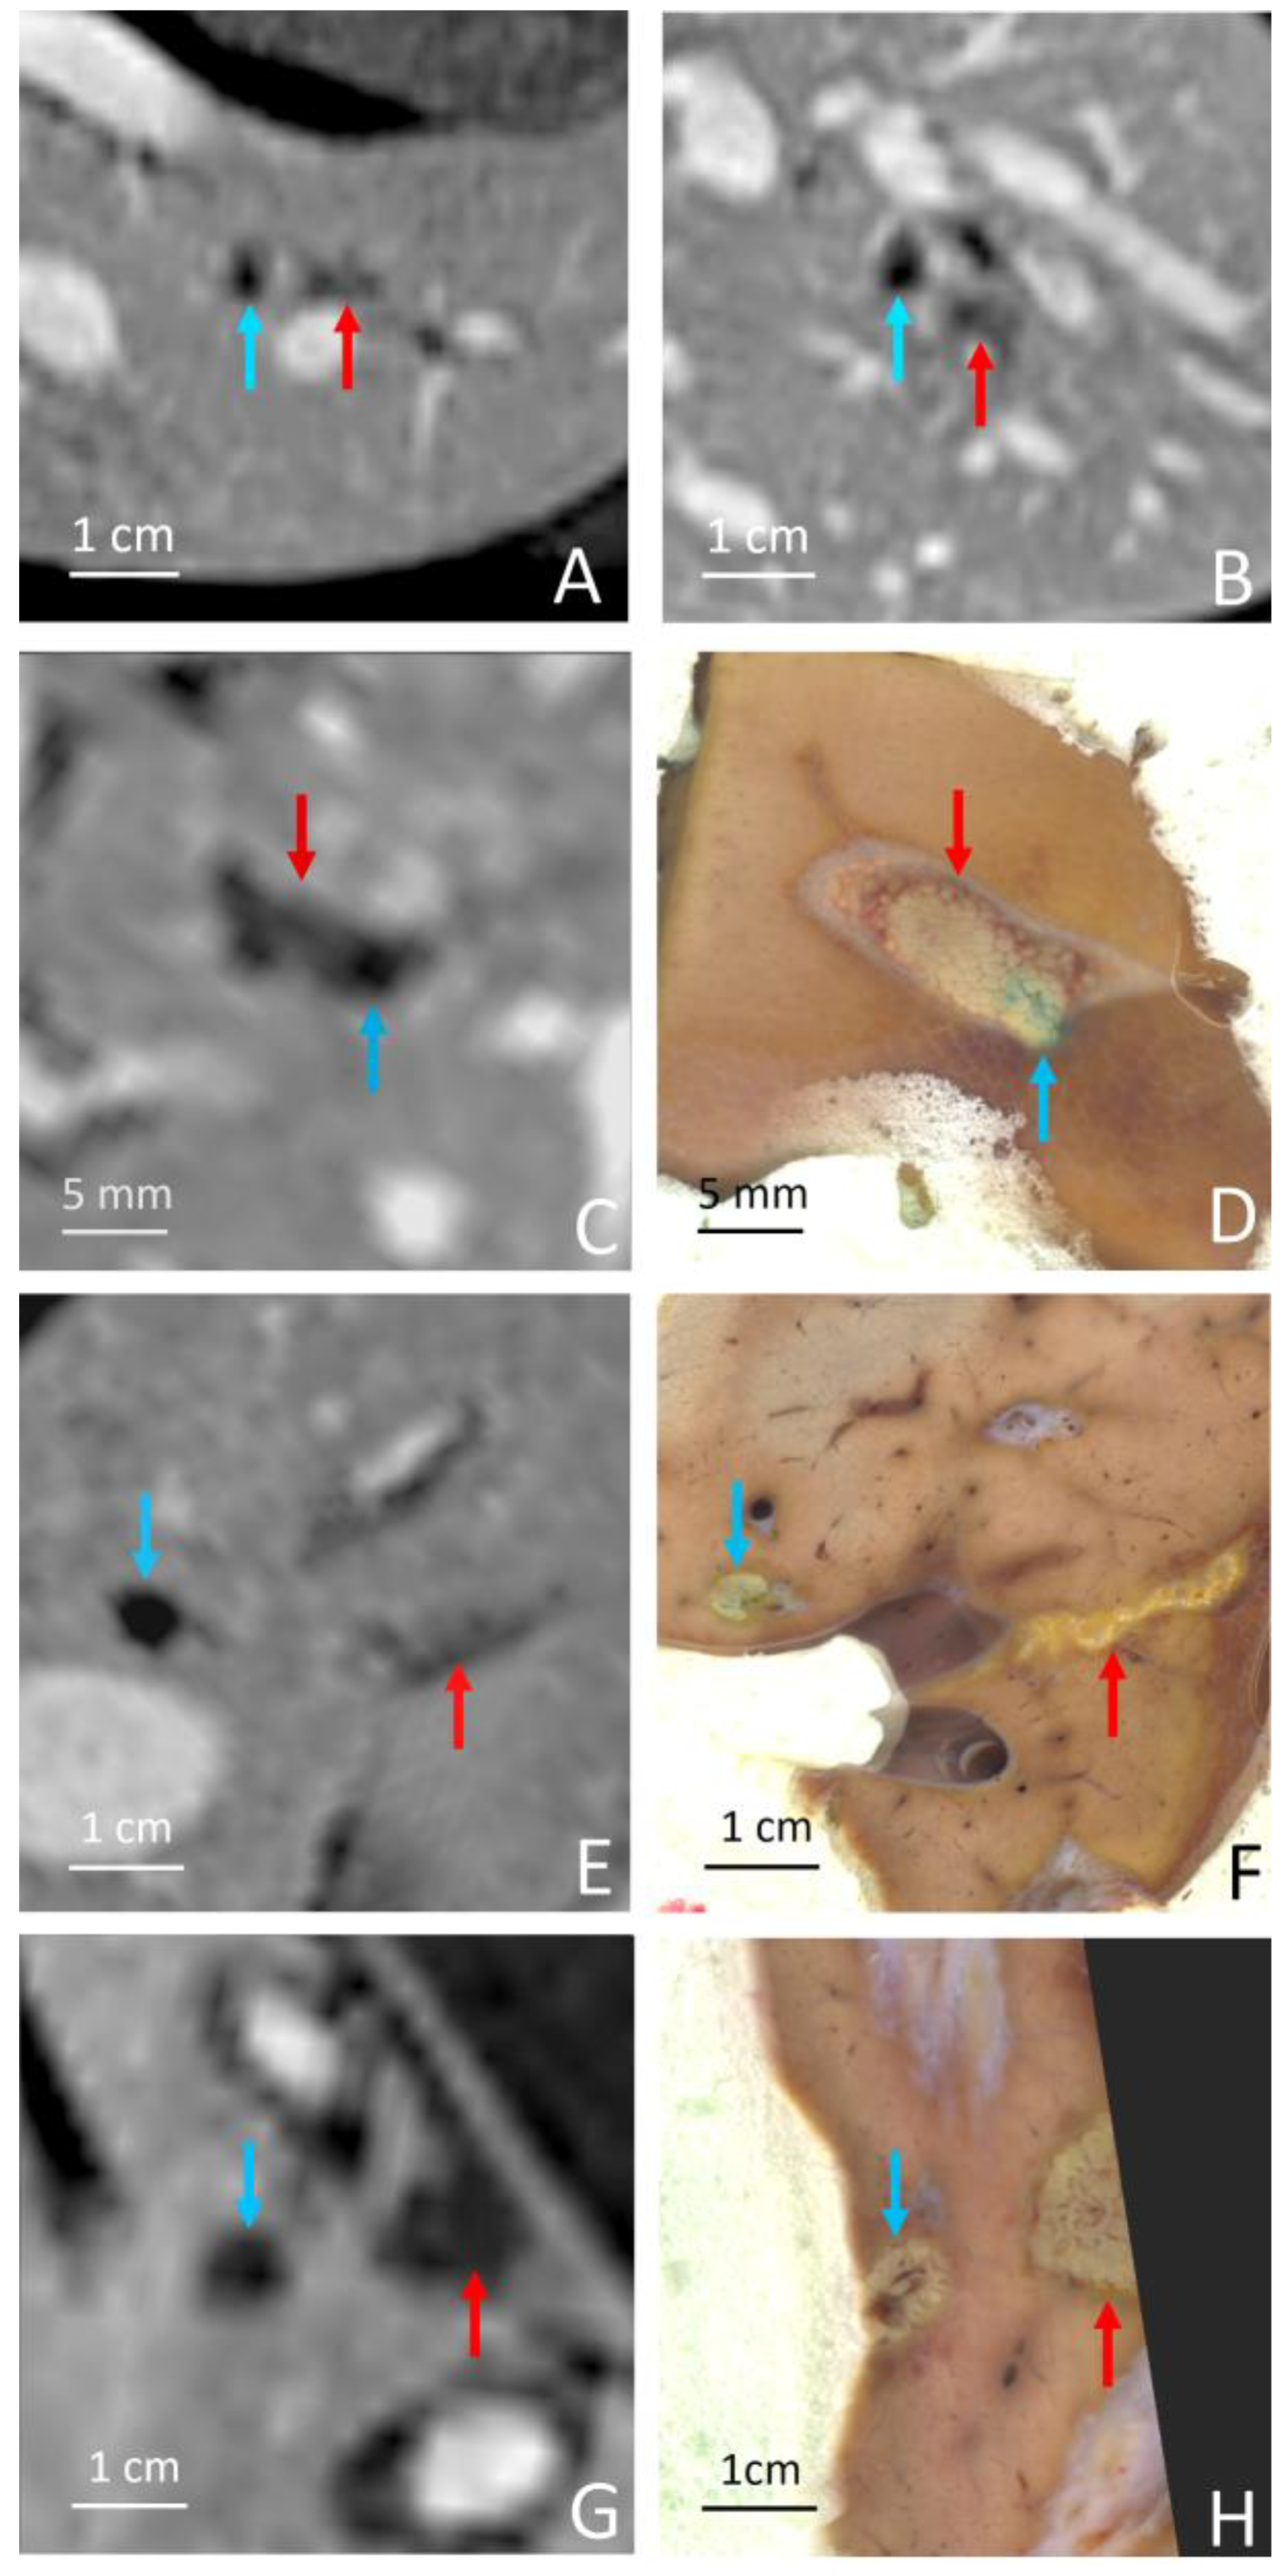

| Grade | Evidence | Sub-Grade |

|---|---|---|

| 0 | No evidence of near-field thermal lesion | |

| 1 | Thermal lesion on the anterior surface of the bone facing the HIFU transducer | a: DCE MRI only b: necropsy-based visual evidence |

| 2 | Thermal lesion on the entire circumference of the bone | a: DCE MRI only b: necropsy-based visual evidence |

| 3 | Thermal lesion in the surrounding soft tissues juxtaposing the anterior surface of the bone facing the HIFU transducer | a: DCE MRI only b: necropsy-based visual evidence |

| 4 | Thermal lesion in the surrounding soft tissues anterior and posterior to the bone | a: DCE MRI only b: necropsy-based visual evidence |

| Pig | RF Ablation Size (mm3), from MR Images (along AP, LR and HF Axes) | Temperature Reached During HIFU Ablation (°C) | HIFU Ablation Longest Axis (mm) from MR Images; See Figure 6 and Figure 7 | HIFU Ablation Longest Axis (mm), from Gross Pathology; See Figure 6 and Figure 7 | Planned Center-to-Center Distance between the RF and MRgHIFU Ablations (mm), from MR Images | Center-to-Center Distance between the RF and MRgHIFU Ablations (mm), from Gross Pathology | Center-to-Center Distance between the RF and MRgHIFU Ablations (mm), from MR Images | Near-Field Side Effects Grade |

|---|---|---|---|---|---|---|---|---|

| 1 | 4.9 × 6.1 × 4.8 | 63 | - | - | 0 | - | - | 1a |

| 2 | 7.2 × 6.3 × 9.2 | 86 | 6.9 | - | 11.8 | - | 10.1 | 1a |

| 3 | 4.6 × 3.7 × 4.5 | 85 | 15.8 | 16.5 | 6.7 | 3.6 | 3.2 | 1a |

| 4 | 6.7 × 6.1 × 6.8 | 86 | 7.4 | 7.9 | 16.1 | 16.0 | 16.2 | 1a |

| 5 | 5.1 × 4.7 × 6.2 | 62 | 21.1 | 23.2 | 18.4 | 24.2 | 24.1 | 1a |

| 6 | 3.0 × 4.6 × 5.5 | 58 | 14.0 | 15.0 | 11.2 | 10.3 | 10.3 | 1b |